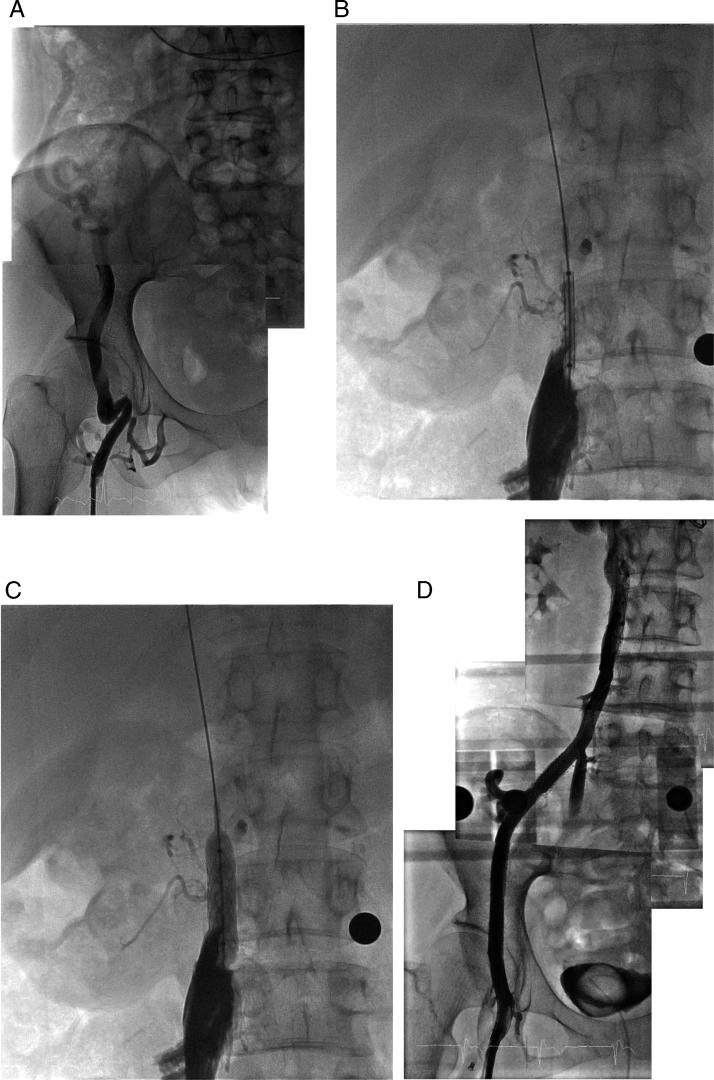

Implantation of ileofemoral stents: A novel approach for bilateral occlusions of the iliofemoral vein in a patient with a Glenn operation.

HeartRhythm Case Rep. 2015 Dec 24;2(2):138-141. doi: 10.1016/j.hrcr.2015.11.010. eCollection 2016 Mar.